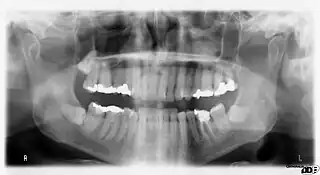

![]() (Ortopantomografía) Radiografía de la boca de un hombre. | ||